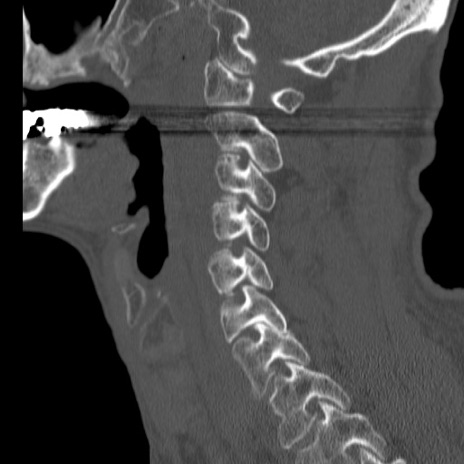

症例46 頚椎CT(矢状断像)

【症例】80歳代男性

【主訴】両側頚部〜上肢のしびれ

【現病歴】昨日、自宅内で転倒、その後より上記症状あり。意識障害なし。

【身体所見】両側上肢のallodynia(熱痛覚過敏)あり。MMTおよびDTRは正確な所見取れず。両上肢の挙上はなんとか可能。

異常所見と診断は?